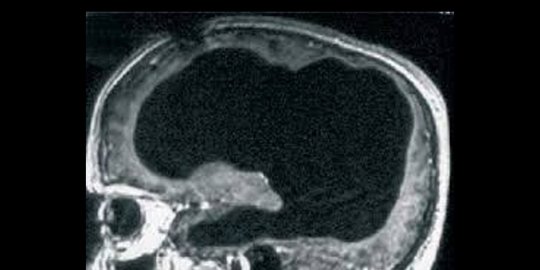

Pria yang hidup dengan (hampir) tak punya otak

Seorang Pria Perancis berusia 44 tahun menderita sakit kaki, dan akhirnya pergi ke dokter untuk periksa. Ketika dilakukan pemeriksaan scan CAT, dokter menemukan sebuah hal yang menarik.

Otak dari pria yang tak disebutkan namanya ini hanya tersisa 10 persen saja dari keseluruhan otaknya. Akhirnya diketahui bahwa dulunya pria ini terjangkit hidrosephalus ketika umur 14 tahun, dan telah diobati dengan teknik bernama shunt. Masalahnya, cairan shunt tersebut ternyata terus mengisi otaknya setelah 30 tahun ke depan dan pelan-pelan mengikis otaknya.

Meski cuma 10 persen dari otaknya yang masih tersisa, ternyata dia tetap hidup dan sehat lahir dan batin. Ilmuwan awalnya kebingungan, namun akhirnya melahirkan hipotesa bahwa otak manusia akan selalu 'terus-menerus belajar.' Hal ini juga membuktikan meski otak adalah organ terpenting dari manusia, otak ternyata cukup fleksibel.